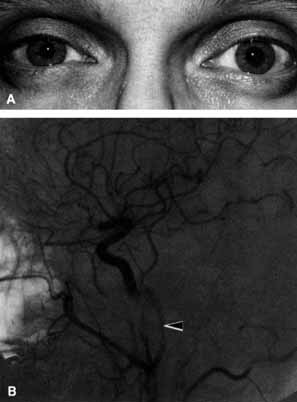

A 40-year-old man developed severe, unrelenting, right-sided headache 1 month after falling from a roof. He noted ptosis and a small pupil coincident with onset of the headache (Fig. 27A). The arteriogram disclosed a narrowed internal carotid artery compatible with the diagnosis of a carotid artery dissection (Fig. 27B).

Fig. 27 A. Right-sided Horner's syndrome (miosis and ptosis) caused by an internal carotid artery dissection. B. Arteriogram demonstrates a narrowed right internal carotid artery (arrow) compatible with a carotid artery dissection.

An example of referred pain and Horner's syndrome is the carotid artery dissection syndrome.49 When the dissection occurs the patient generally develops unilateral referred orbital pain, ptosis, and a miotic pupil but without anhidrosis (see Fig. 27A). Typically, dissection occurs in the older, vasculopathic patient or days to weeks after head trauma. The symptoms are similar to those of cluster headache, that is, recurrent unilateral severe headache and oculosympathetic paresis, the difference in carotid artery dissection being unrelenting pain and unresponsiveness to normal migraine therapy. Arteriogram or magnetic resonance imaging are useful for documentation of the carotid artery dissection (see Fig. 27B).